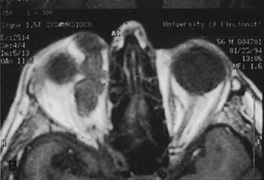

Although intraconal lesions medial to the nerve sometimes can be approached laterally, great care to identify and protect the optic nerve is required during deep orbital dissection. Because the eyelid crease incision allows such wide exposure of the superolateral orbit, it is often possible to remove fairly large orbital lesions without removing the lateral orbital wall (Fig. 9). Surgery in this case proceeds as described to exposure of the superior and lateral bony orbital rims. It is not necessary to reflect periosteum over the external surface of the rim. Instead, once periosteum at the rim is exposed, it is cut with cautery and then only the mesial periorbita need be elevated internally to expose orbital contents with subsequent intra-orbital dissection carried out with the lateral rim in place. Often it is preferable to initially attempt to remove intraconal or lacrimal fossa lesions in this fashion. If exposure proves inadequate, the periosteum over the external surface of the lateral orbital rim can be elevated and osteotomies and removal of the lateral wall still can be carried out.

Fig. 9. A,B. Coronal and axial CT images of a large intraconal neoplasm. C. Because it was felt to represent a well-encapsulated cavernous hemangioma, this lesion was a candidate for removal via an eyelid crease orbitotomy without bone removal. The eyelid crease incision marked. D. Incision made with scalpel. E. Orbicularis muscle is tented up and incised to expose the underlying septum. F. Dissection of a skin-muscle flap deep to orbicularis exposes the orbital septum and superior orbital bony rim. G. Cutting cautery is used to incise periosteum along the superior and lateral rims; finger palpation of the bone helps to direct this incision. H. Periorbita is elevated along the mesial surface of the lateral orbital rim in order to expose the deep orbital tissues. I. The cavernous hemangioma is visualized in the wound. Retraction is provided by one or more malleable retractors. J. Cryoprobe is affixed to the hemangioma to facilitate manipulation of the lesion. K. Large cavernous hemangioma after removal through the eyelid crease incision which was accomplished without bone removal. L. Periorbita is reattached over the lateral rim. M. The eyelid crease incision is closed with a running suture.